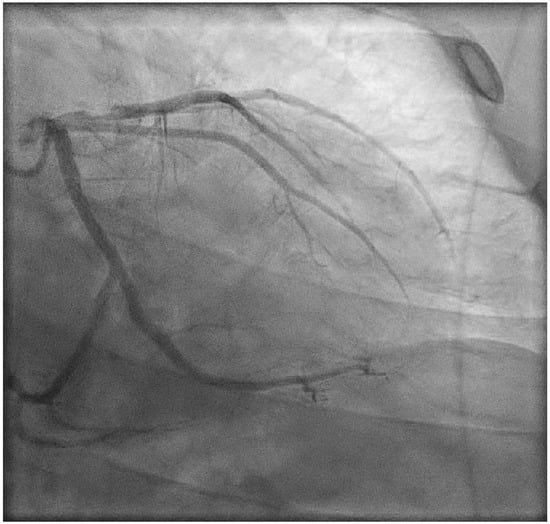

2. Case Presentation